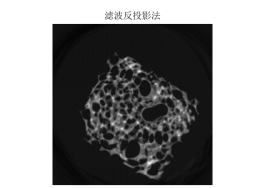

图 9

图 10

图 11

由滤波公式与原来灰度像素矩阵每一列进行卷积,得到了消除边缘失锐的灰度像素矩阵再用原本未滤波的模型进行图形重建运算,程序见附录程序四,结果以及效果如下:

图 14

图 15

图 16

5.3.2模型建立与求解

误差以及原因已经分析完,下面自行建立一个模版对本模型进行检验和阐述,利用matlab函数自动获取一个头骨图形仿体,对仿体的灰度像素矩阵进行拆分,拆分成本题附件所给CT扫瞄的接受数据形式,然后再行图形重建,先利用原来未滤波的模型再进行滤波模型重建,程序见附录程序五,结果如下图:

图 17

图 18

图 19